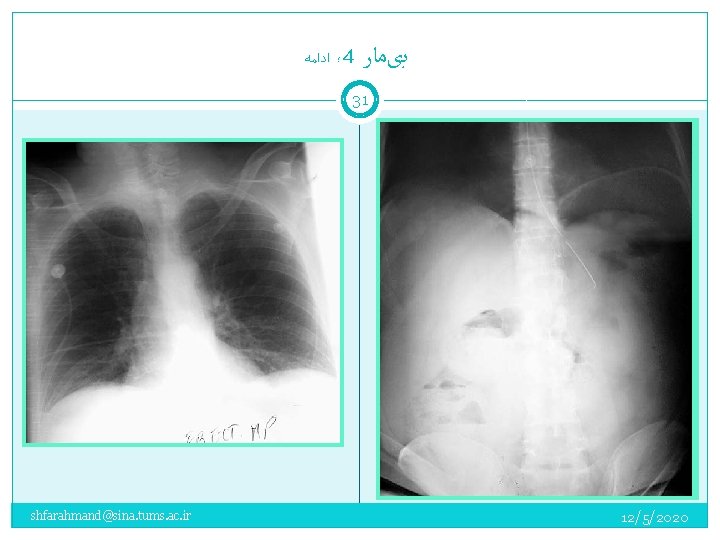

؛ ﺍﺩﺍﻣﻪ 4 ﺑیﻤﺎﺭ 30 A 51 -year-old man presented to the ED with progressive abdominal pain of one day's duration. He had not eaten all day and had vomited twice. There was no associated diarrhea or melena. He had a history of alcoholic hepatitis, COPD, and surgical repair of a colonic-bladder fistula 10 years earlier. He had mild constipation and abdominal discomfort for the past few months. On examination, the patient was in moderate distress due to abdominal pain. Vital signs: BP: 130/70 mm Hg; PR: 118/min; RR: 24/min; temperature 100. 8 ؛ F (rectal). His abdomen was distended but soft, with mild diffuse tenderness and no rebound tenderness. His stool was negative for occult blood. He was anicteric. shfarahmand@sina. tums. ac. ir 12/5/2020

؛ ﺍﺩﺍﻣﻪ 4 ﺑیﻤﺎﺭ 31 shfarahmand@sina. tums. ac. ir 12/5/2020

پﻨﻮﻣﻮپﺮیﺘﻮﺋﻦ 32 ﻋﻠﻞ ﺯﺧﻢ پپﺘیک ﺳﻮﺭﺍﺥ ﺷﺪﻩ 80% ( ﺣﺴﺎﺳیﺖ %60) ﻫﻤﻪ ﻣﻮﺍﺭﺩ ﻗﺎﺑﻞ ﻣﺸﺎﻫﺪﻩ ﻧیﺴﺖ pneumatosis cystoides ، ﺍﺯ ﻋﻠﻞ ﻧﺎﺩﺭ intestinalis shfarahmand@sina. tums. ac. ir Perforated peptic ulcer (usually duodenal) Gastric ulcer perforation (benign or malignant) Large bowel obstruction causing cecal perforation Cecal or sigmoid volvulus Perforated appendicitis or diverticulitis (infrequent) Colonoscopy and biopsy Residual postoperative gas Ruptured pneumatosis cystoides intestinalis Extension from pneumomediastinum 12/5/2020